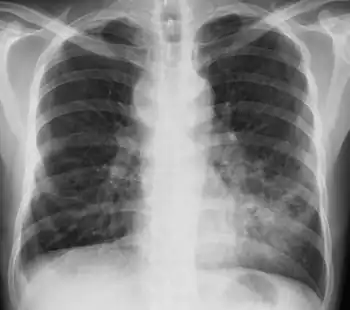

MAC usually affects patients with abnormal lungs or bronchi. However, Jerome Reich and Richard Johnson describe a series of six patients with MAC infection of the right middle lobe or lingula who did not have any predisposing lung disorders.[18][19]

The right middle lobe and lingula of the lungs are served by bronchi that are oriented downward when a person is in the upright position. As a result, these areas of the lung may be more dependent upon vigorous voluntary expectoration (cough) for clearance of bacteria and secretions.

Since the six patients in their retrospective case series were older females, Reich and Johnson proposed that patients without a vigorous cough may develop right middle lobe or left lingular infection with MAC. They proposed this syndrome be named Lady Windermere syndrome, after the character Lady Windermere in Oscar Wilde's play Lady Windermere's Fan. However, little research has confirmed this speculative cause.[20]

- Chest X-ray or CT scan showing evidence of right middle lobe (or left lingular lobe) lung infection